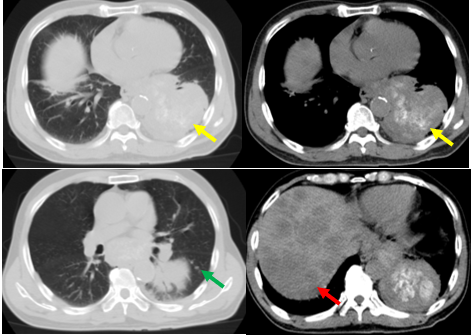

Hình 2: Hình ảnh cắt lớp vi tính cho thấy khối thùy dưới phổi trái sát rốn phổi kích thước 75x63mm (mũi tên vàng), nốt đặc thùy dưới phổi trái 4mm (mũi tên xanh) và các khối giảm tỷ trọng lan tỏa nhu mô gan theo dõi thứ phát (mũi tên đỏ)

Kết quả phát hiện thấy ở nhu mô thùy dưới phổi trái, sát rốn phổi có khối tổn thương kích thước 75x63mm, ngoài ra rải rác nhu mô thùy dưới có vài nốt đặc, nốt lớn đường kính 4mm và có nhiều hạch trung thất.

Tại gan: nhu mô gan có các khối nốt giảm tỷ trọng trước tiêm, kích thước lớn nhất 75x104mm (theo dõi tổn thương di căn).